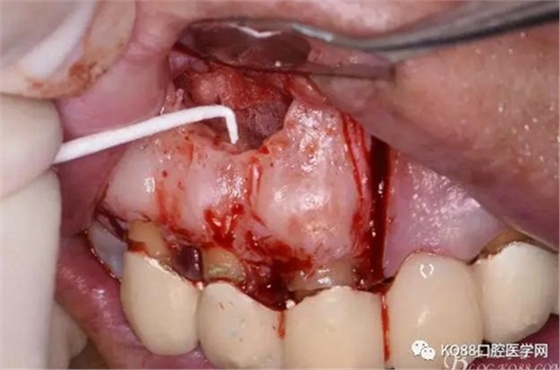

圖13.根尖倒預(yù)備

圖14.吸潮紙尖干燥根管

圖15.取愛如特生物陶瓷材料